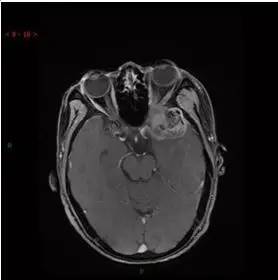

MRI增强轴位